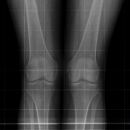

Ganzbeinaufnahme a.-p.

Qualitätskriterien

Vollständige Darstellung des Beckens, der Hüftgelenke bis runter zum Fuss. Für Winkelmessungen am Hüftgelenk ist es wichtig, dass Trochanter major und minor gut sichtbar sind.